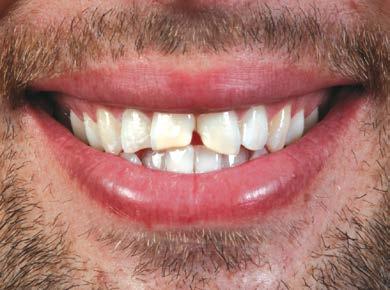

Las carillas BruxZir Esthetic fueron justo lo que el paciente esperaba y la emoción por su nueva sonrisa era evi dente (Figura 15).